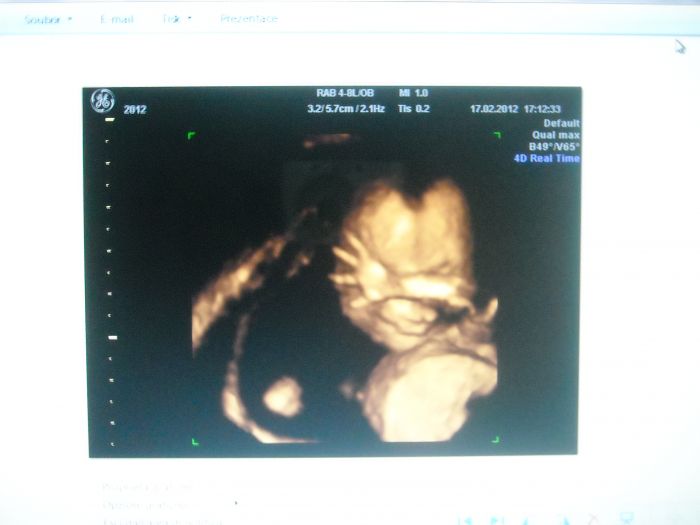

ahoj holky tak jsme byly na tom UZ podle UZ vse absolutne v poradku, mozek srdce ,kosti ma i delsi nez odpovida tydne, podle tohoto lekare miminko absolutne v poradku.Nicmene muj soukromy doktor rika ze i miminka co vypadaji normalne uz mely down takze se ty plodovky drzi jak hovno kosile.Takz e v pondely tam naklusu i kdyz mam strasnej strach a budu se modlit abych nepotratila a hlavne aby se potvrdilo ze je zdrave...pridavam fotecku a pridavam ze je to moje tolik vytouzena holcicka Sofinka

[100215] Petruško, to je krásná fotečka, jak má ručičku před obličejíčkem!